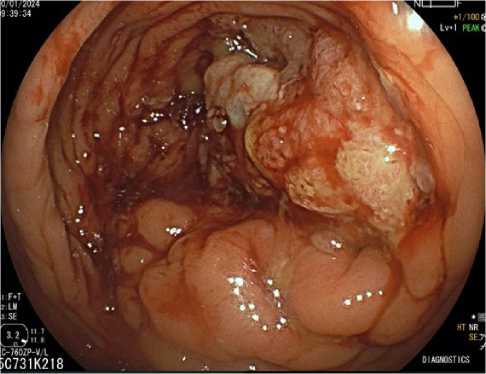

Помимо этого, пациенту проведена видеоколоноскопия: в просвете верхнеампулярного отдела прямой кишки сохраняется стенозирующая опухоль (рис. 11). По результатам гистологического исследования биоптатов опухолевых клеток не выявлено, фрагменты грануляционной ткани с участками слизистой оболочки толстой кишки (рис. 12).

Рис. 11. Результаты видеоколоноскопиии на фоне иммунотерапии пембролизумабом у пациента 38 лет с диагнозом метастатический колоректальный рак с признаками микросателлитной нестабильности; по данным трепан-биопсии опухолевых клеток не обнаружено (10 января 2024 г.)

Fig. 11. Results of video colonoscopy during immunotherapy with pembrolizumab in a 38-year-old patient diagnosed with metastatic MSI-H colorectal cancer; no tumour cells were detected after trephine biopsy (10 January 2024)